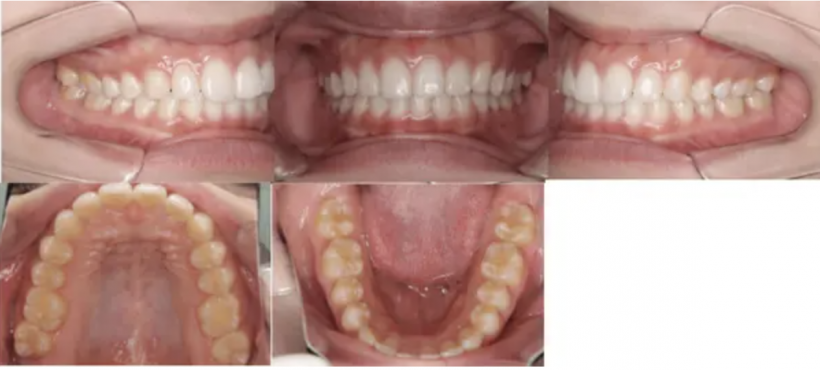

治療例①部分矯正: 28歳

【治療前】

【治療後】